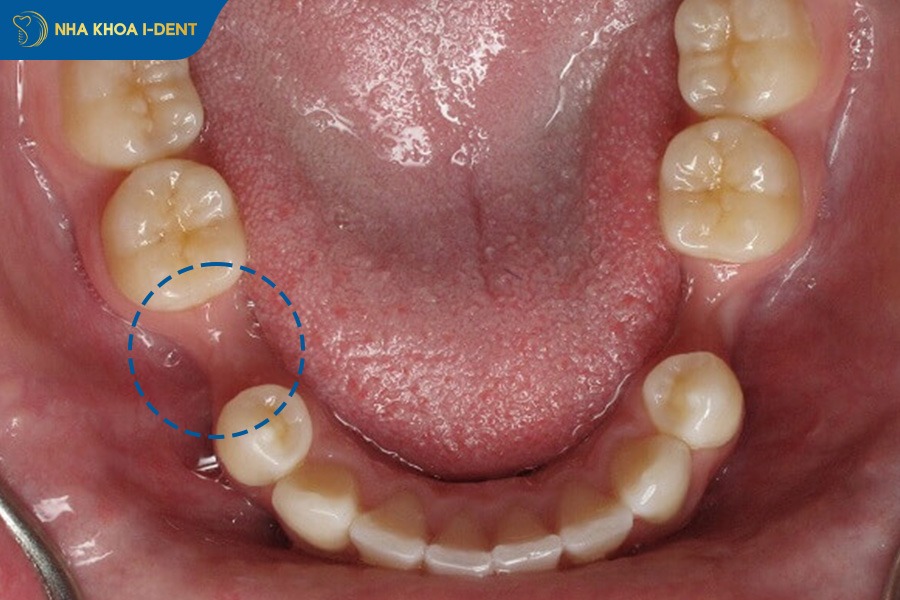

Răng xô lệch là hậu quả diễn ra do các răng bên cạnh di chuyển về phía khoảng trống của răng số 5, đồng thời răng đối diện mọc dài ra dẫn đến mất cân bằng khớp cắn và ảnh hưởng toàn bộ hệ thống răng miệng.

Sau khi mất răng số 5, răng số 4 (phía trước) và răng số 6 (phía sau) sẽ nghiêng về khoảng trống để lấp đầy chỗ trống. Quá trình này bắt đầu sau 6-12 tháng, với tốc độ di chuyển khoảng 0.5-1mm mỗi năm. Răng số 5 hàm đối diện sẽ dần dần mọc dài xuống vì không còn lực cắn cản trở. Khi răng di chuyển và mọc lệch, khớp cắn không còn đều trên toàn bộ hàm răng dẫn đến một số răng chịu áp lực quá mức làm mất cân đối cung hàm, sai lệch khớp cắn và rối loạn khớp thái dương hàm.